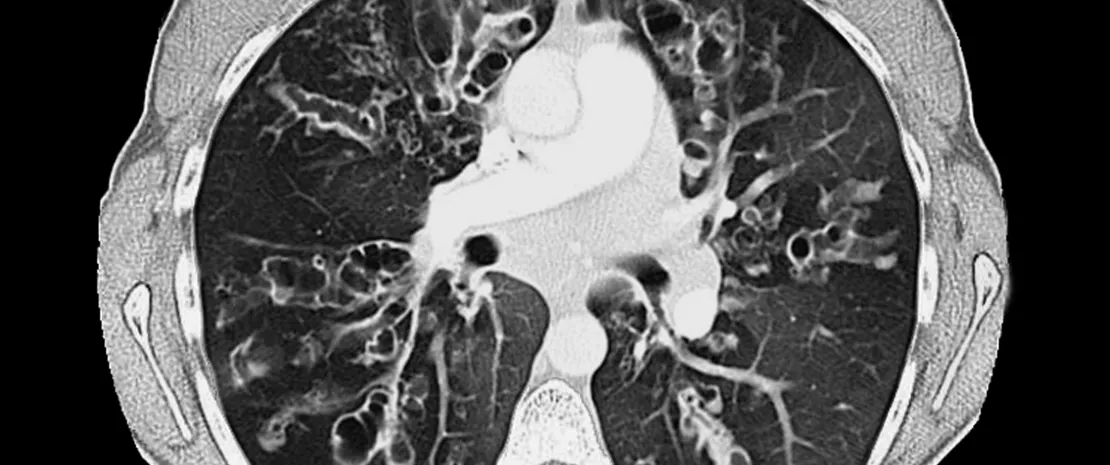

Respiratory microbiota and pulmonary infections associated with cystic fibrosis

Recent technical progress in molecular screening, sequencing and metagenomic analyses are contributing to the detailed characterization of human respiratory tract microbiota. This growing precision is accompanied by a better understanding of the complex relationships between the different populations of microorganisms and the respiratory system of their host, whether the latter is healthy or not. In this respect, cystic fibrosis is a good illustration. Pulmonary infections, which play a determining role in the pathogenesis of the disease, display changes over time. Relatively benign infections with Staphylococcus aureus and Haemophilus influenzae in early childhood, can progress to persistent infections with Gram-negative bacteria such as Pseudomonas aeruginosa, which become increasingly severe with age. This progression is accompanied by harmful changes in the respiratory tract microbiota and raises an underlying question: are these dysbioses the consequences of infectious episodes, or do they contribute to their development?

In the absence of answer regarding causal relations, a literature review has identified the differences between a healthy respiratory microbiota and a microbiota disrupted by cystic fibrosis.14 The first is diversified and characterized by a predominance of one or two bacterial genera among the following: Staphylococcus, Dolosigranulum, Corynebacterium, Haemophilus, Streptococcus and Moraxella. The last three expose patients to a higher risk of developing acute respiratory infections. In contrast, children with cystic fibrosis have a less dense and less diversified bacterial environment, marked by the predominance of Corynebacterium and Streptococcus. This dysbiosis seems to become more pronounced with time and disease severity, and the terminal phase can be associated with the presence of only one or two pathogens.